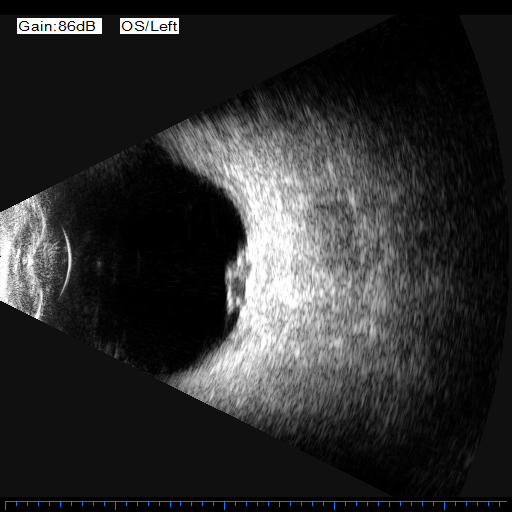

眼科特检师胡燕娟护士给患儿进行了相关检查,发现患儿眼前段照相有双眼颞上颞下球结膜下出血;眼底照相显示:患儿右眼眼底静脉血管末端出血,左眼眼底可见黄斑区有一黄白黑相间的肿块,合并视网膜脱离、视网膜下积血;双眼球B超示患儿左眼视网膜下积血,左眼视网膜脱离,疑是左眼脉络恶性色素瘤?